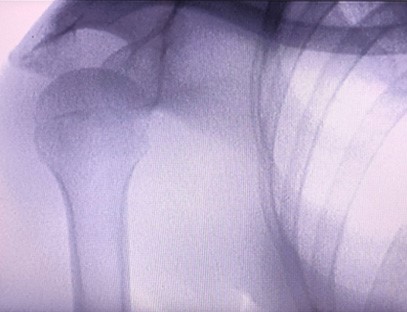

インスタントイメージングポータブルX線装置整形外科クリニック向けに特別に設計された、四肢のX線撮影を行う医療機器です。X線の透過性と人体のさまざまな組織間のX線吸収レベルの違いを利用して、内部構造情報を視覚画像に変換し、医師の診断と治療を支援します。特に、個人クリニック、獣医、ペット病院に適しています。四肢撮影X線装置は、ペット医療で使用され、獣医師の病気の診断と治療を支援します。

専門分野:整形外科クリニックのニーズに合わせて設計されており、特にX線画像手、手首、肘、肩、膝、足首などの手足。

鮮明な画像:高度なデジタル画像技術を使用して高品質のX線画像を提供し、医師が病状を正確に診断するのに役立ちます。